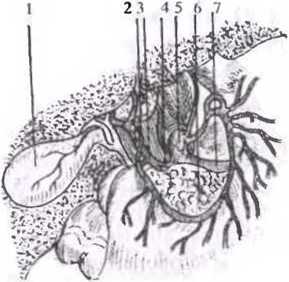

Анатомия и особенности Гартманова кармана желчного пузыря